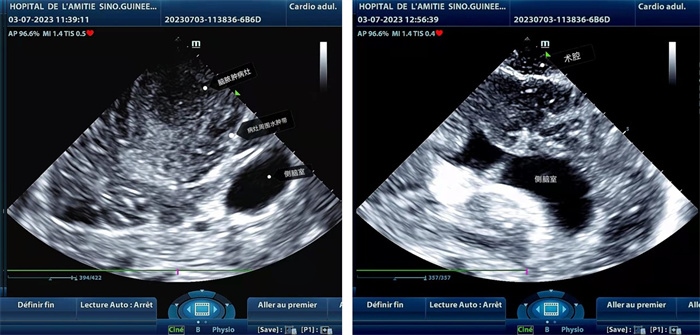

手術(shù)中,張國濱在超聲科顧秀娟的幫助下,運用顱腦術(shù)中超聲技術(shù),通過將一次性保護套的超聲探頭置于腦組織表面,實時觀察病變的位置和形態(tài),進一步確認最佳手術(shù)路徑。術(shù)中超聲顯示,病變位于左額頂葉,大小約為4x4x3cm,邊界清晰,呈囊實性,周邊腦組織水腫明顯。最終,病灶順利切除,診斷為腦膿腫,并通過超聲檢測確認術(shù)腔無病變殘留、無出血,為患者術(shù)后恢復提供了良好的保障。

左圖顯示術(shù)中超聲見囊實性病變,大小約為4x4x3cm,病灶周圍腦組織水腫明顯;右圖為病灶切除后,術(shù)中超聲示術(shù)腔無病變殘留

左圖顯示術(shù)中超聲見囊實性病變,大小約為4x4x3cm,病灶周圍腦組織水腫明顯;右圖為病灶切除后,術(shù)中超聲示術(shù)腔無病變殘留。中國第二十九批援幾內(nèi)亞醫(yī)療隊供圖